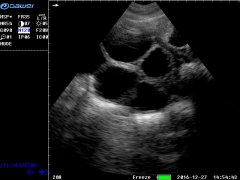

大為便攜式彩色獸用B超儀照出圖效果

徐州市大為電子設(shè)備有限公司是集自主研發(fā)、生產(chǎn)、銷售醫(yī)用超聲、獸用B超產(chǎn)品于一體的專業(yè)廠家。大為獸用B超經(jīng)過快10年的發(fā)展,產(chǎn)品更新?lián)Q代,質(zhì)量突...